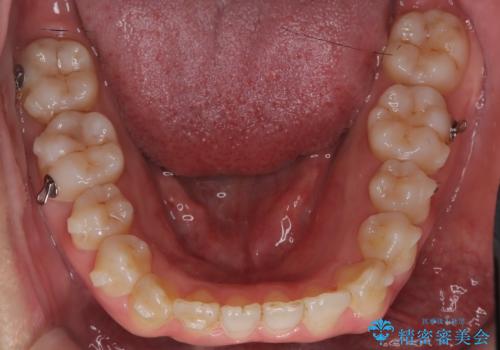

抜歯をせずに口元の突出感を改善するためには、奥歯を後方に動かして前歯を引くスペースをつくる必要があります。そこで、インビザラインによるマウスピース矯正に加え、TAD(矯正用アンカースクリュー)を併用する治療計画を立てました。TADを固定源とすることで、効率的に奥歯を後方へ動かし、非抜歯でも前歯をしっかり引き下げることが可能になります。

治療はまず精密スキャンとシミュレーションを行い、TADを使用して奥歯を遠心移動(後方へスライド)させる設計を組み込みました。マウスピースは計画に沿って順次交換し、TADと連結しながらコントロールすることで、歯列全体を無理なく整えていきました。

前歯の傾きが改善され、横顔の印象が大きく変化。上下の正中も一致し、かみ合わせのバランス(臼歯関係)も整いました。目立たず快適に治療ができた点にもご満足いただき、「人に気づかれずにここまで変化できるとは思わなかった」とのお声をいただいています。治療後はリテーナーを用いて、仕上がりをしっかり保っています。

インビザラインでも、TADを併用することでより精密な歯の移動が可能になります。